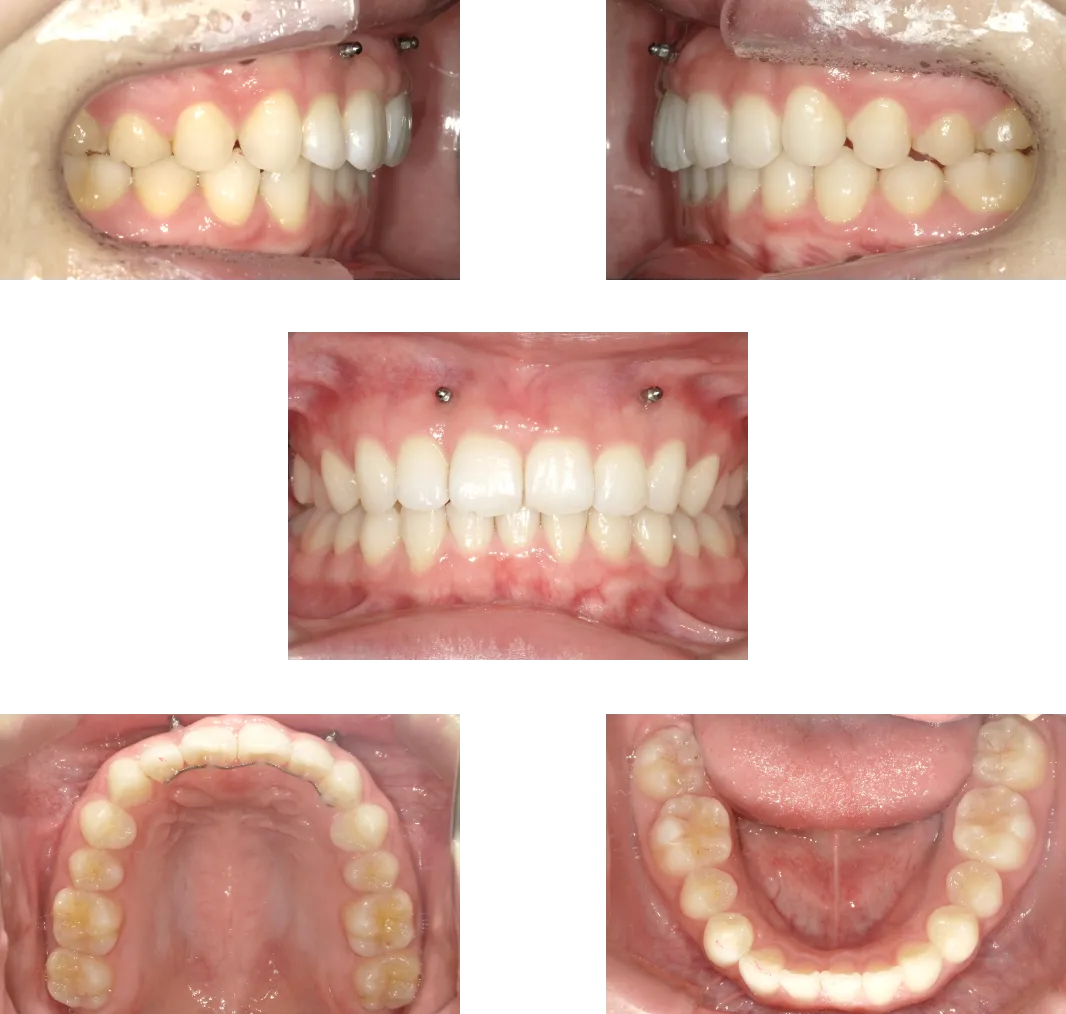

上顎前突 -7歳-

• Before

• After

診断

過蓋咬合を伴う重度骨格性上顎前突

治療期間

2年

抜歯

なし

料金

600,000+550,000円(調整料を含む。2期開始時分析料別途発生)

リスク

痛み、軽度の歯根吸収、術後の変化